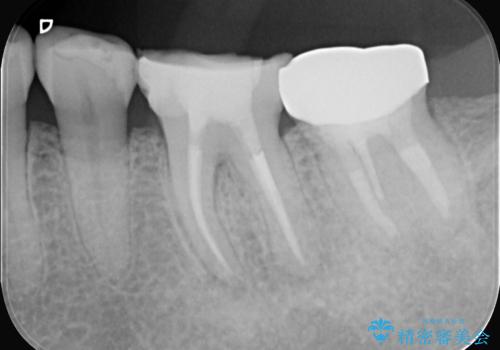

- 2日前から歯の痛みが続くという主訴でご来院されました。診察の結果、**不可逆性歯髄炎(歯の神経の重度の炎症)**と診断。レントゲンでは、歯髄腔が狭くなり、根管が石灰化している難症例であることが確認されました。患者様の大切な歯を残すため、歯科用顕微鏡を用いた精密根管治療を行うことで、狭く、見えにくい根管を正確に探し出し、治療を完了させる計画を立案しました。

今回の治療は、特に難易度の高い石灰化した根管が対象でした。まず、治療中の細菌感染を防ぐためにラバーダムを使用。次に、歯科用顕微鏡で治療部位を何十倍にも拡大しながら、狭窄した根管の入り口を探し、慎重に拡大・清掃を行いました。顕微鏡を用いることで、肉眼では不可能だった根管内部の細かい構造を確認しながら、感染源を徹底的に除去することができました。これにより、難症例の奥歯でも再発リスクを抑えた適切な処置を行うことができ、治療後に痛みは解消。大切な歯を長期間にわたり保存することができました。